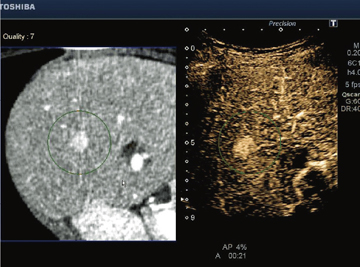

Realtime Application Platformとは,高速リアルタイム処理を実現し新アプリケーションを可能とするプラットフォームである。Elastographyをはじめ,びまん性肝疾患の評価に期待される当社独自のASQ(Acoustic Structure Quantification)をリアルタイム化(図4,5)。また,エコー像とCT像/MRI像を連動させ,病変の検出および治療支援に有効な"Smart Fusion"に対応している(図6)。このSmart Fusionは,通常のコンベックスプローブ以外にマイクロコンベックスプローブ,穿刺用コンベックスプローブにも対応しているため,早期発見から治療までを幅広くサポートする(図7)。また,磁気送信機は装置一体型のアームに取り付けるため,省スペースで移動も楽に行える(図8)。これらの機能により,病変の検出および質的診断に期待が持たれている。

![]() 図6 Smart Fusion(エコー像とCT像を連動させた肝細胞がん) |